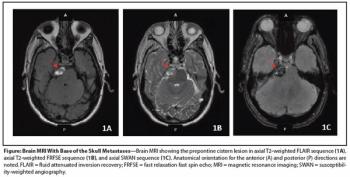

A Rare Case of Metastatic Renal Epithelioid Angiomyolipoma

ByElaine T. Lam, MD,Francisco G. La Rosa, MD,Thomas D. Suby-long, MD,Kimi L. Kondo, DO,Shandra S. Wilson, MD,L. Michael Glodé, MD, FACP,Thomas W. Flaig, MD The patient is a 43-year-old man who was initially evaluated at an outside institution for unexplained anemia and who was found to have a large right kidney mass. He underwent a radical nephrectomy for a 19-cm large-cell, poorly differentiated neoplasm, consistent with pleomorphic, epithelioid angiomyolipoma (EAML) with extensive necrosis and cytologic atypia.